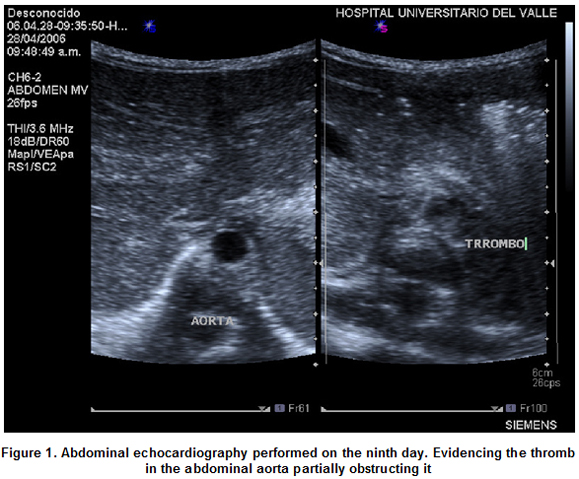

The case was present at the Neonatal Unit (CIRENA) of the Hospital Universitario del Valle. Corresponds to a masculine neonatal of 34 weeks, weighing 2,035 g, hospitalized for presenting signs of breathing difficulties, for which the umbilical venous and arterial catheterization was performed. On his fourth day of life, the patient presents high blood pressure and on the seventh day acrocyanosis is evidenced, absence of pulsations and arterial tension in the lower limbs is not present. on the eighth day the umbilical catheters are removed, the patient continues to be hyper tense and changes in his lower limbs, previously described are present. Echocardiography is performed observing a thromb at the aorta level. The diagnostic was confirmed on the ninth day by means of a doppler echocardiography (Figures 1, 2) which evidenced a thromb partially compromising the aorta and completely compromising the left renal artery by not detecting blood flow to the left kidney.